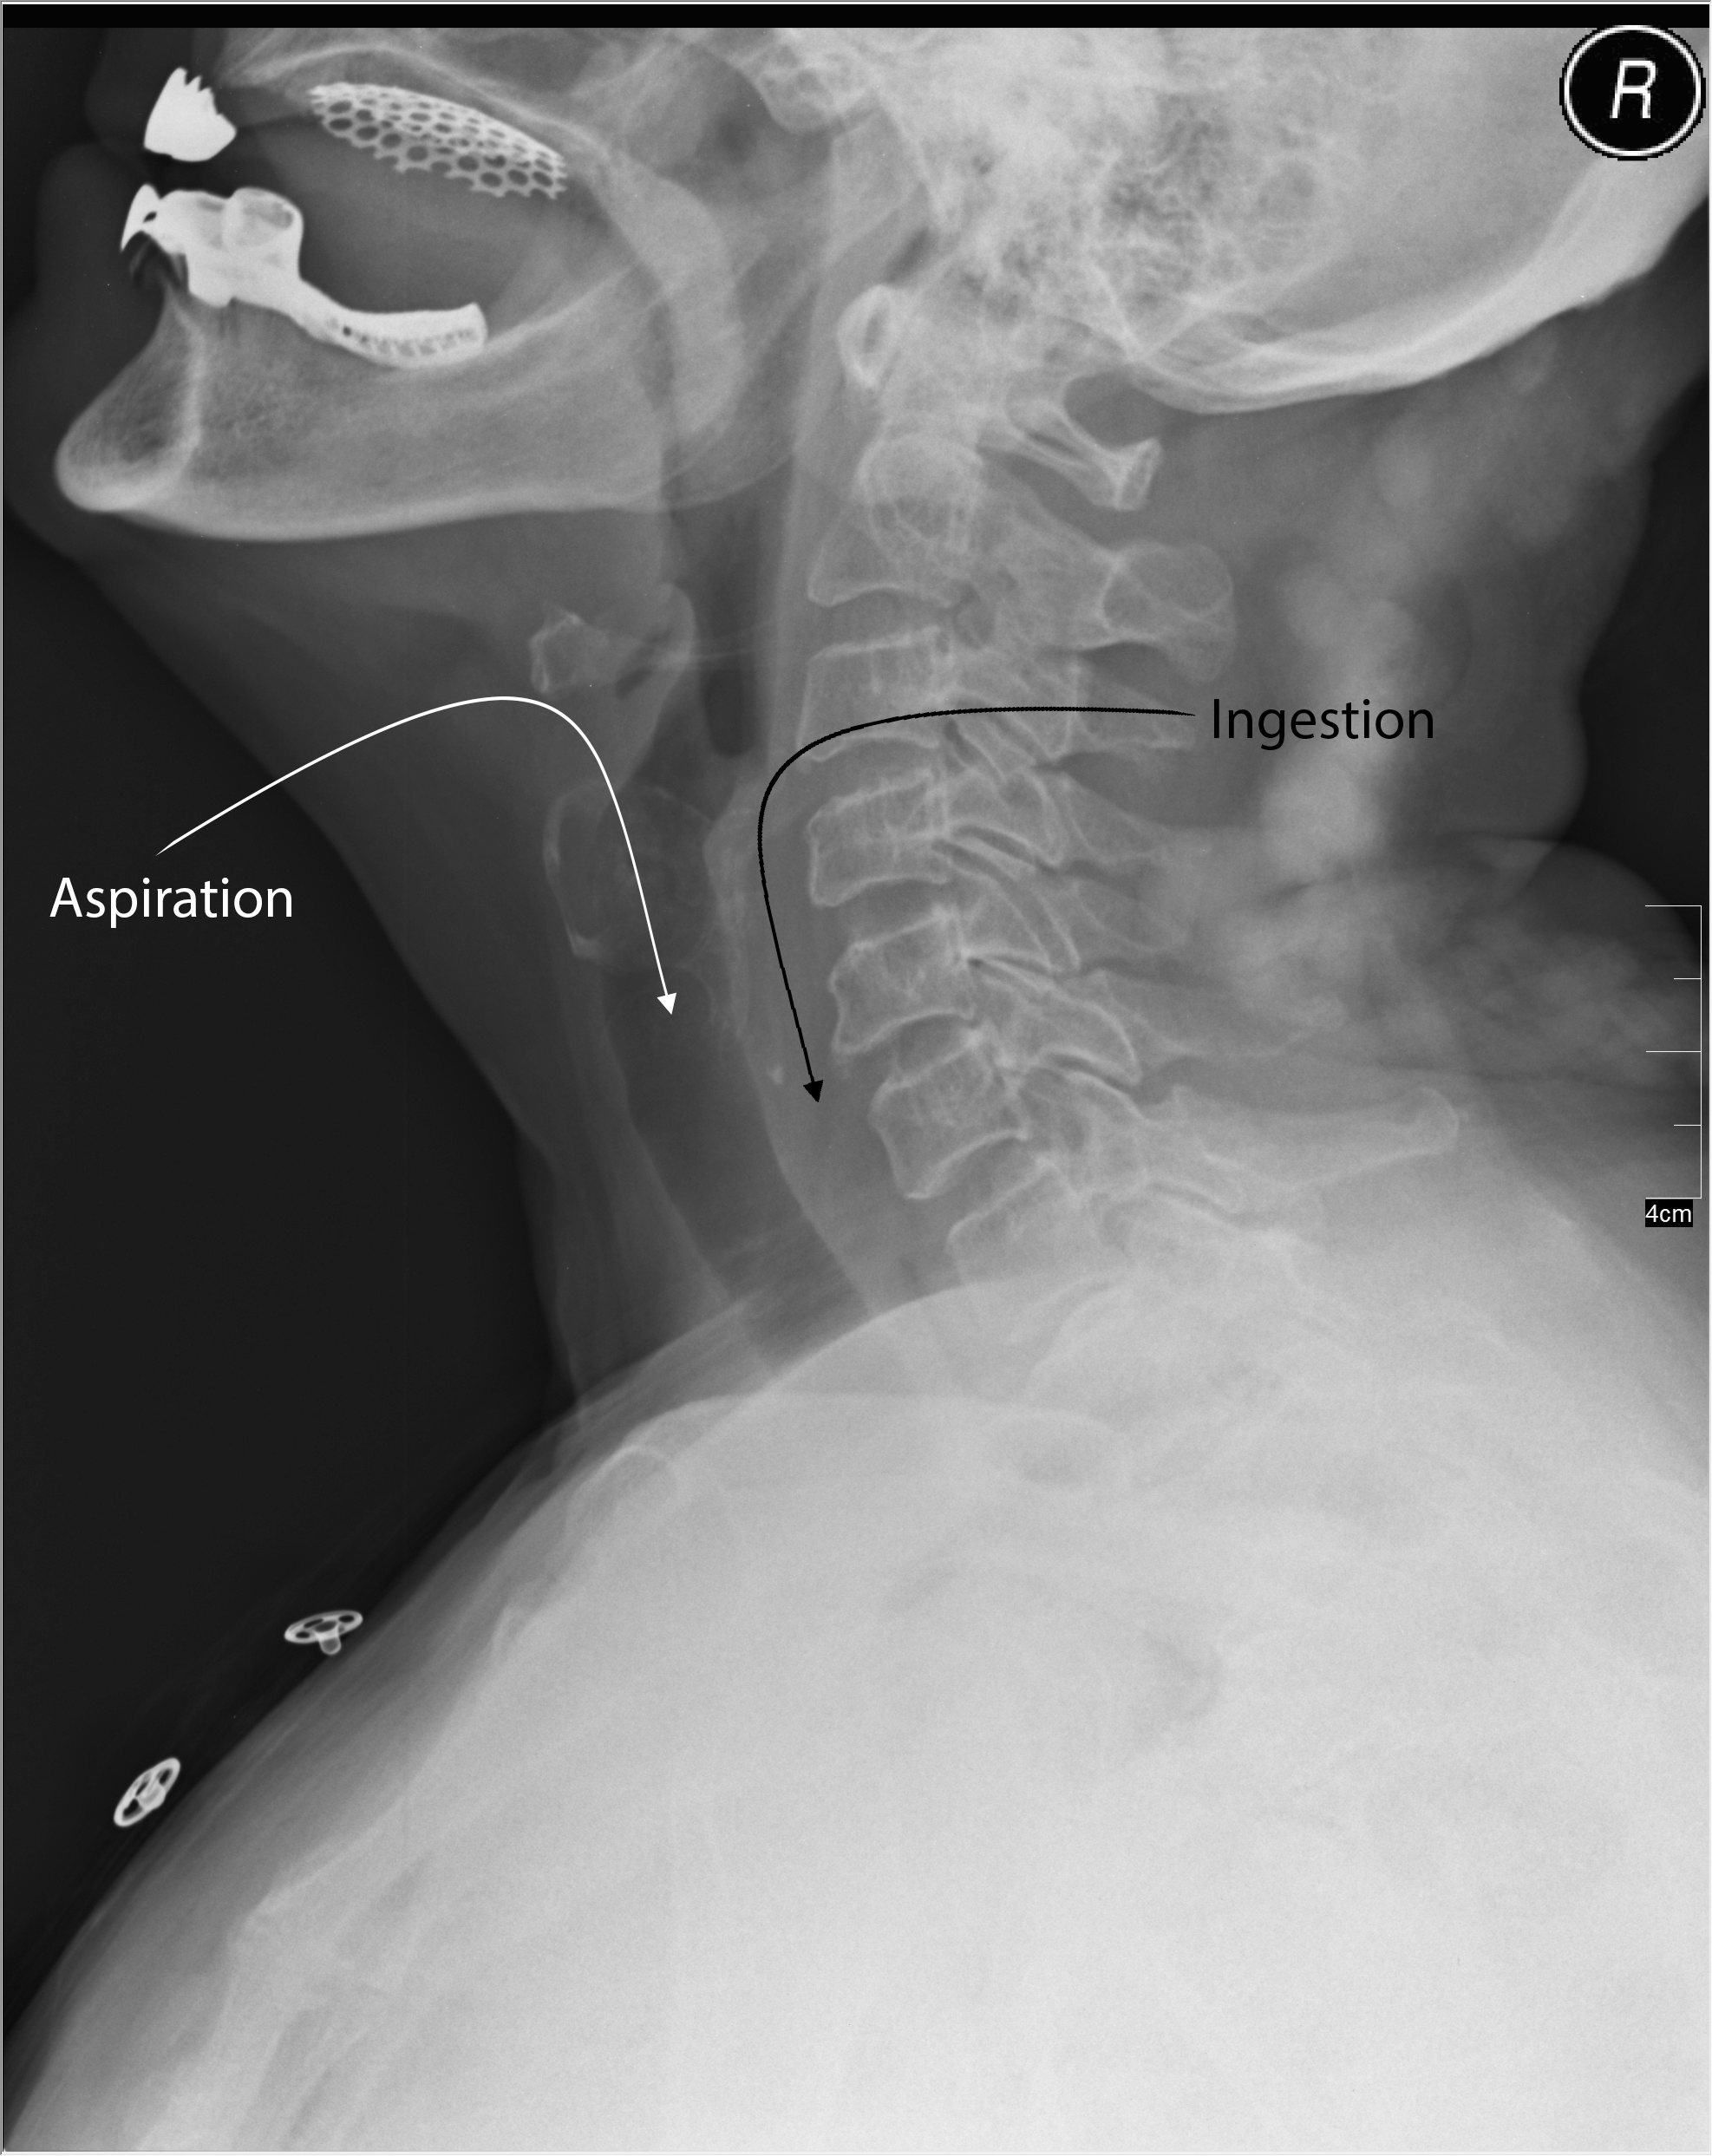

If the patient is appropriately aged, inspiratory and expiratory films also can be obtained. Those films can demonstrate hyperinflation of the lung that contains the foreign body, although data are mixed on these films as well.9,10 Lateral neck soft tissue plain radiographs also can be obtained to help determine where the foreign body is located.11,12 As seen in Figure 1, the column of air indicates the trachea, whereas just posterior to it would be the location of the esophagus. A hyperdense object in either of these locations would indicate the likely location of the foreign body.11,12

Figure 1. Lateral Neck Soft Tissue Plain Radiographs for the Detection of Foreign Body |

Adapted from Dilmen N. Medical X-ray imaging UEY07 nevit. Published 2011. https://commons.wikimedia.org/wiki/File:Medical_X-Ray_imaging_UEY07_nevit.jpg. Creative Commons Attribution-ShareAlike 3.0 Unported (https://creativecommons.org/licenses/by-sa/3.0/deed.en). |